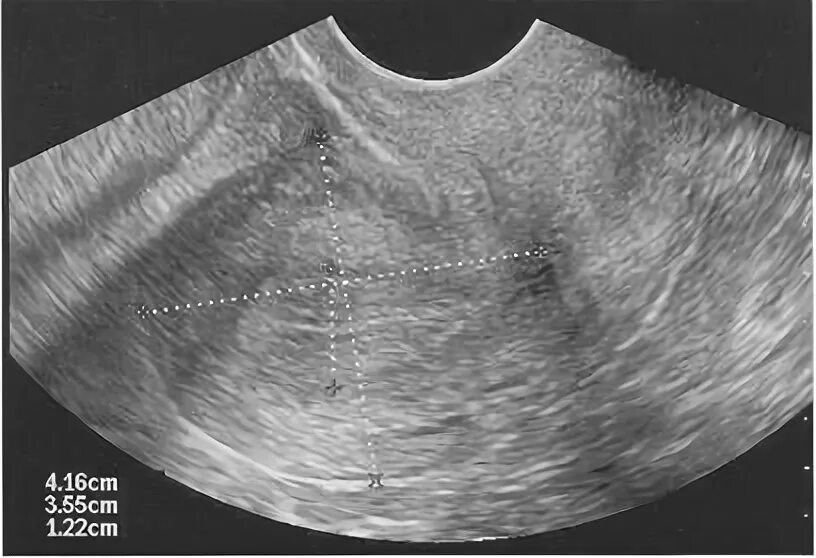

Диффузные изменения миометрия что это